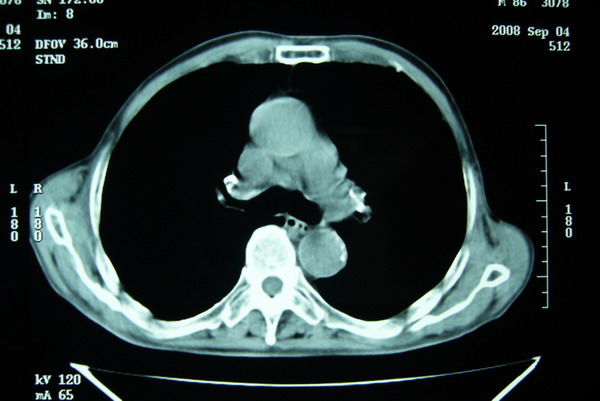

标题: CT15579:男 86岁 咳嗽 咳少量白痰 发热2天 吸烟史60年 [打印本页]

标题: CT15579:男 86岁 咳嗽 咳少量白痰 发热2天 吸烟史60年

右肺上叶巨大软组织肿块,轮廓不规则,纵隔内有肿大淋巴结,首先考虑肺癌。